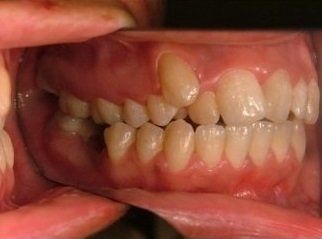

Il trattamento ortodontico non è solo per i bambini: se hai denti storti, affollati, mancanti o prominenti che ti impediscono di masticare e parlare liberamente, potrebbe essere necessario rivolgersi a uno specialista. L’ortodonzia prevede l'uso di apparecchi ortodontici, che possono essere fissi o rimovibili.

L’ortodonzia non dimentica neanche l’importanza dell’estetica e la sicurezza che un bel sorriso può portare. Per questo un apparecchio può avere come obiettivo anche quello di riportare il profilo facciale nella posizione più corretta possibile e di restituire al paziente un aspetto migliore, oltre che la fiducia in se stesso.